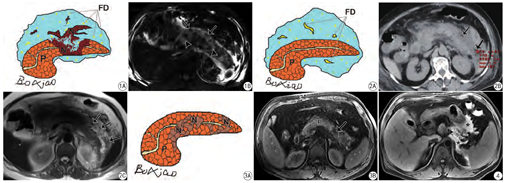

既往谈到坏死性胰腺炎,总想到“胰腺本身”坏死的严重度,即Balthazar提出的基于胰腺实质坏死程度的评分系统。然而,新亚特兰大共识将胰腺坏死重新划分为3个亚型:(1)胰腺和胰周坏死型/混合型(图1);(2)仅胰周坏死型(图2);(3)仅胰腺坏死型(图3)。尽管混合型在临床上最多,但后面两种亚型也需留意。正如近年来Meyrignac等[9]提出的胰周坏死量比Balthazar提出的胰腺坏死评分更适合AP严重度判定和预后分析。

虽然在2012亚特兰大分类中未提及关于AP出血的术语,但病理学上仍划分为水肿性与出血坏死性胰腺炎(即病理上坏死灶的形成常伴随出血灶)。在临床工作中,发现胰周脂肪坏死合并出血是能够被影像学检出的。尽管早期发现这一病理状态可能不会影响患者的治疗,但笔者前期研究发现影像学上发现的胰腺/胰周出血(图4)与AP的严重程度有较好的相关性[3],对预后判定有帮助。

AP除了腹膜后间隙的相应变化外,还要观察腹膜下间隙的改变。对此笔者开展过临床研究:AP易累及横结肠系膜(发生率为61.9%)(图5);横结肠系膜评分(TMI score)与MRSI评分及APACHE-II评分均具有较好的相关性[6]。此外,AP也容易累及小肠系膜(发生率为67.9%)(图6);小肠系膜评分(MI score)与MRSI评分和APACHE II评分也具有较好的相关性[7]。这些腹膜下间隙受侵犯的征象同样有助于本病预后的评估。